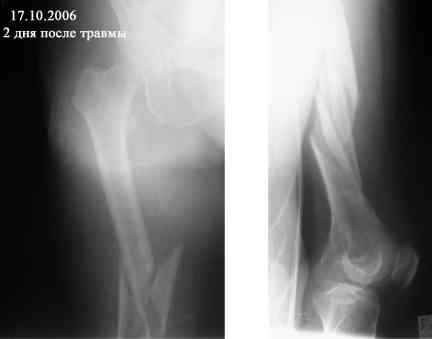

Re: Оскольчатый перелом бедра. Помогите определиться с дальнейшей тактикой

Представляю вашему вниманию снимки в динамике